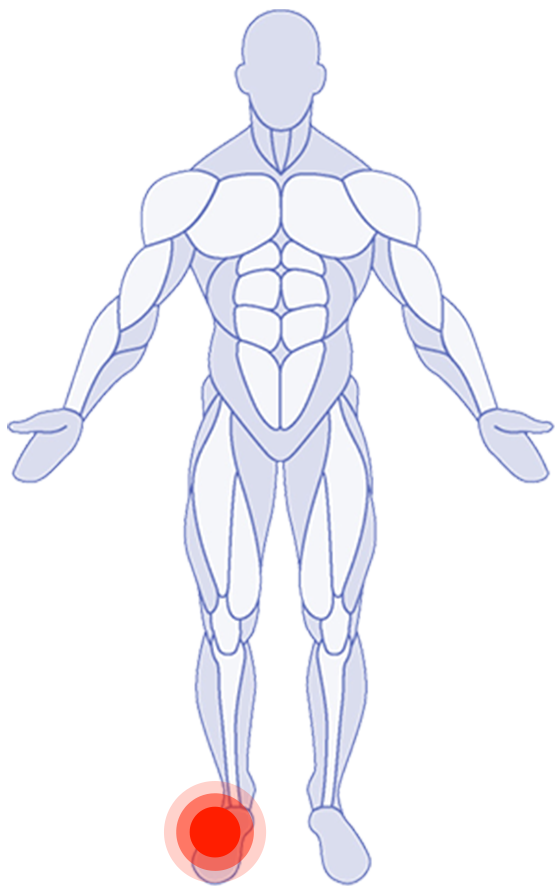

Where do you need attention?